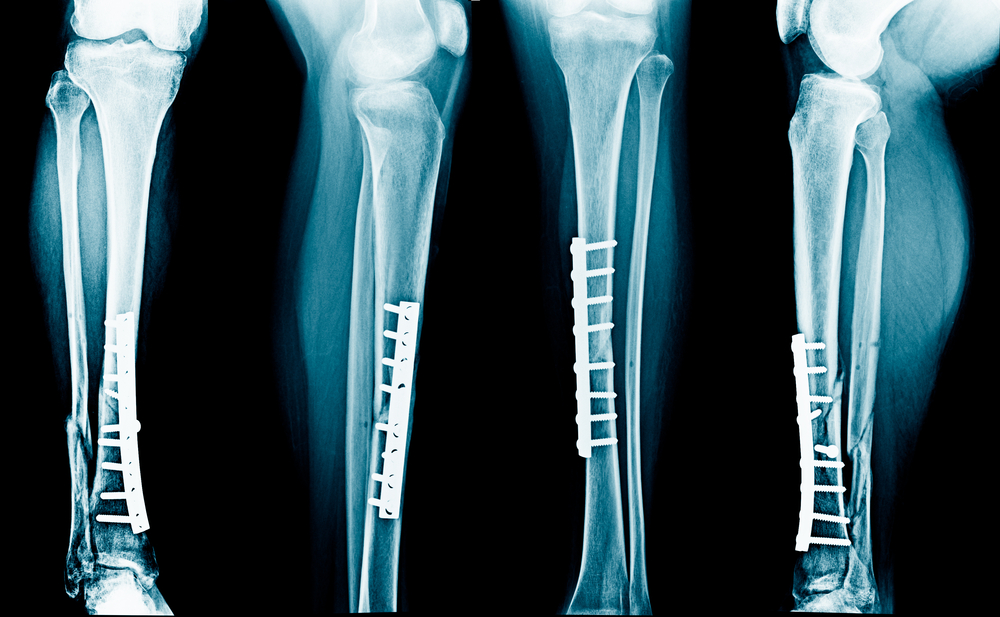

- Vidinė fiksacija – operacijos metu kaulai sutvirtinami specialiomis plokštelėmis, vinimis ar sraigtais